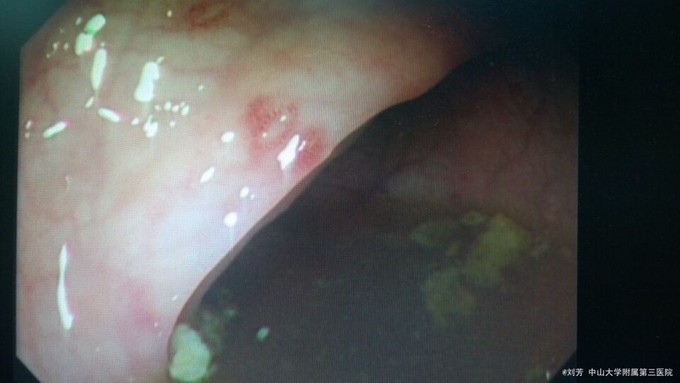

患者在外院诊断为系统性血管炎,查cANCA弱阳性,在我院查ANCA四项阴性,诊断证据不充分,也曾诊断为自身免疫性肝炎,但其自免肝的抗体指标阴性,总体来说,患者的诊断不明确。患者出现了发热、腹泻、肝脾大等症状和体征,予对症支持治疗,其CRP和血清补体等指标偏高还是提示体内存在免疫异常,在排除结核、肝炎、病毒感染后,暂予小剂量激素治疗,同时行纤维结肠镜检查,提示肠黏膜炎性病变,予柳氮治疗,密切观察病情。